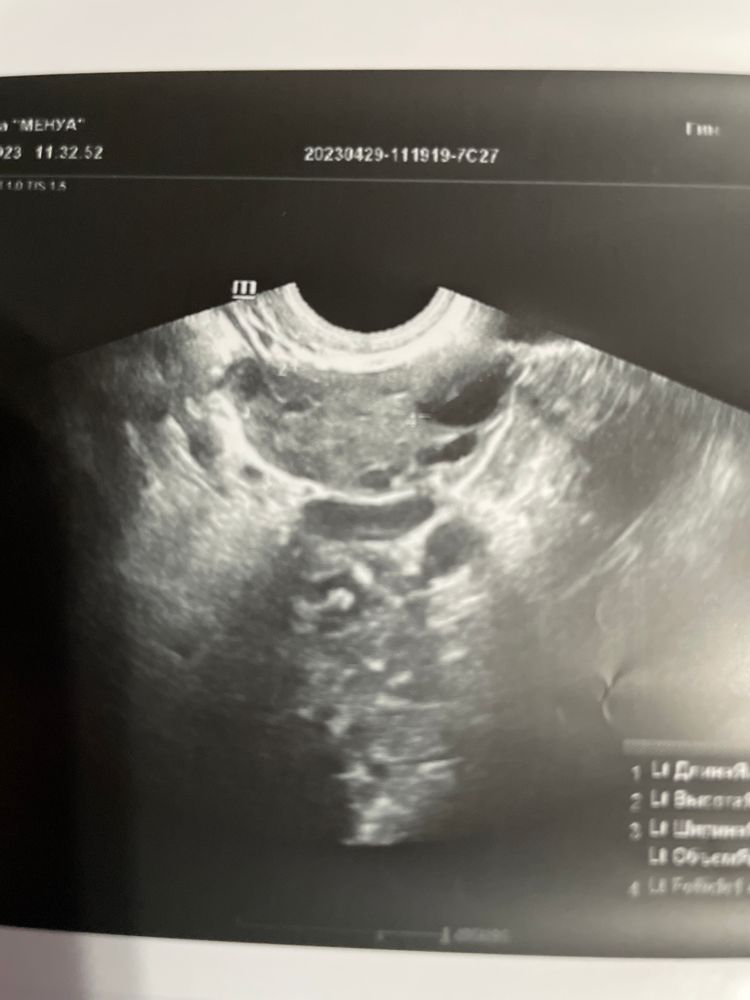

Девочки подскажите ,больше на целый фолликул или жт похоже ?

но и своя овуляция была всегда ) вопрос именно в этом цикле что-то непонятное по заключениям узи